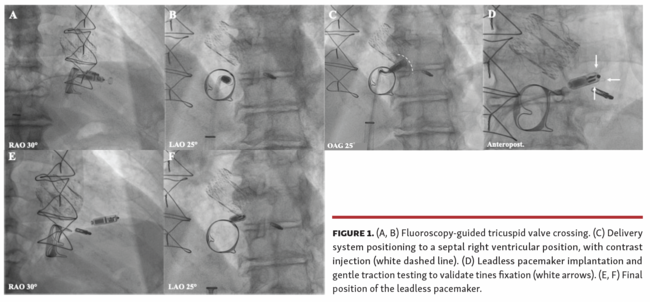

An 81-year-old patient with previous transcatheter aortic valve replacement, transcatheter mitral valve repair, and conventional biological tricuspid valve replacement presented with symptomatic complete atrioventricular block. Pacemaker implantation was performed under mild sedation, through a 27 Fr outer-diameter right femoral venous sheath. Fluoroscopy-guided tricuspid valve crossing (Video 1) was performed using the Micra Transcatheter Pacing System (Medtronic) (Figures 1A, 1B), with a right ventricular septal positioning (Figures 1C). After device fixation and traction testing (Figures 1D), the tether was cut and the delivery system was removed (Figures 1E, 1F). Postoperative pacemaker parameters were good and the patient had no pathological tricuspid valve regurgitation.